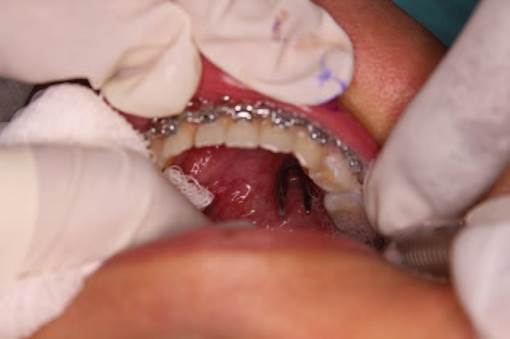

Técnica quirúrgica: derivación mediante secuencia de Hernández Altemir,2,5 considerando la regla 2-2-2 pro puesta por Nyáràdy (incisión de 2cm de largo, a dos centímetros de la línea media y dos centímetros medial a una paralela con la mandíbula en la región submentoniana) (Figura 1). Se realiza disección roma con pinza, en contacto con la cara lingual de la mandíbula hasta llegar al piso de la boca, desplazando los músculos cutáneo del cuello y milohioideo, creando un túnel intraoral por el cual pasa el TET; la exteriorización del TET se realizó con el uso de un hemostato (Figura 2). Se fija TET a la piel con sutura de Nylon 3-0. Se corrobora la adecuada posición del TET y se conecta al circuito anestésico (Figuras 3 y 4). El tubo se transfiere de nuevo a la posición oral antes de la extubación completa. Se realiza el cierre de la incisión submentoniana (Figura 5), mientras que el cierre intraoral no es necesario.2

Figura 3 Fijación del TET y colocación de conector de TET para posterior conexión al circuito anestésico (Caso 1).

Técnica quirúrgica: derivación submentoniana con igual técnica al caso 1 (Figuras 6-10).

Figura 7 Incisión intraoral con pinza para la creación del nivel submentoniano (Caso 2).